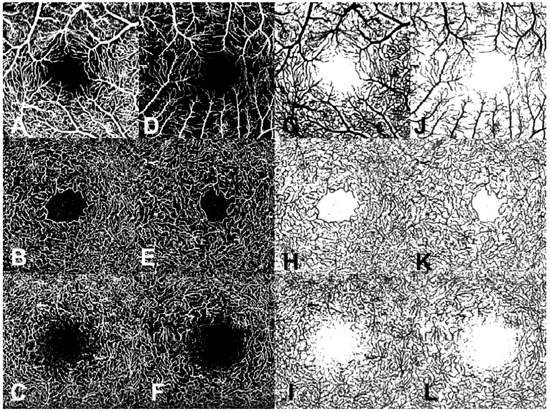

2.3. OCTA en Face Image Analysis